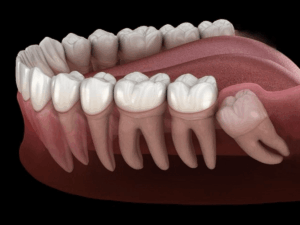

Due to limited space in the jaw, most wisdom teeth don’t have enough room to grow straight. This results in various eruption patterns and potential complications.

3.1 Signs of wisdom teeth growth Lower

Lower wisdom teeth, when misaligned, are notorious for causing prolonged pain, gum inflammation, redness, and pus formation. In some cases, patients find it difficult to open their mouths or experience pain radiating to the ears or neck.